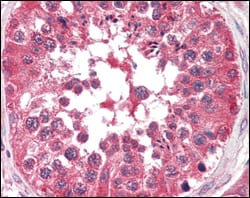

Product Image

IHC | 1/200 - 1/1000 |

BRAF(V-raf murine sarcoma viral oncogene homolog B1 ) is the main effectors recruited by GTP-bound Ras to activate the MEK-MAP kinase pathway. B-Raf contains three consensus Akt phosphorylationsites (Ser364, Ser428, and Thr439).B-Raf is a key regulatory molecule of the mitogen-activated protein kinase kinase (MEK),it has a long amino-terminal region,the region is essential for homo-dimerization of B-Raf and hetero-dimerization of B-Raf and c-Raf at the plasma membrane, followed by phosphorylation of Thr118 in the amino-terminal B-Raf-specific region. Notably, in calcium ionophore-stimulated HeLa cells, B-Raf could propagate signals to MEK under the basal level of GTP-Ras. Expression of Raf-B is highly restricted with highestlevels in the cerebrum and testes and defects in braf are involved in a wide range of cancers.The BRAF gene mutation is frequently detected in papillary thyroid carcinoma,melanocytic nevi,primary cutaneous melanomas and colorectal cancers. |